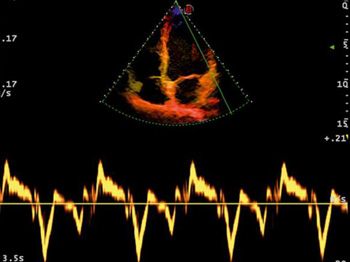

- Тканевый доплер TDI

- Функция STIC: исследование сердца плода в режиме объёмной визуализации

- Функция STIC Color

Цветной доплер. Эта функция поможет в исследованиях сердечно-сосудистой системы. Вы сможете выделить цветом характер кровотока на интересующем вас участке. Кровяной поток, идущий от датчика, отображается синим, к датчику – красным. Турбулентный поток фикс

Тканевый доплер. Данная функция подарит вам возможность оценить сократительную способность миокарда. Как правило, она применяется вместе с импульсно-волновым доплером и помогает при проведении диагностики системных поражений сердца, кардомиопатии, ишемии

Объемная визуализация сердца плода. Эта впечатляющая функция исследования сердца плода основана на достижениях технологии 4D и связана с пространственно-временной корреляцией получаемого вами изображения. Теперь вы сможете сохранять полученные данные для

Постоянно-волновой доплер. Благодаря данной функции вы сможете проводить количественную оценку кровотока в сосудах с высокоскоростными потоками, что активно используется в исследованиях эхокардиографии